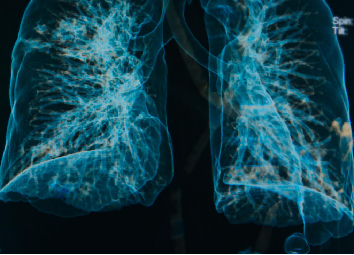

肺部感染的影像学特征

多发性结节伴快速进展

CT表现为双肺多发实性结节(直径0.5-3cm),结节边缘可见毛刺征及分叶征,特征性表现为短期内体积呈几何级数增长(如1周内增大10倍),需与转移瘤、结核球等鉴别。

组织特异性侵袭

肠道为原发感染部位,但菌体可通过血流播散至肺、关节及中枢神经系统,肺部感染时表现为肺泡巨噬细胞大量浸润和肉芽肿形成。